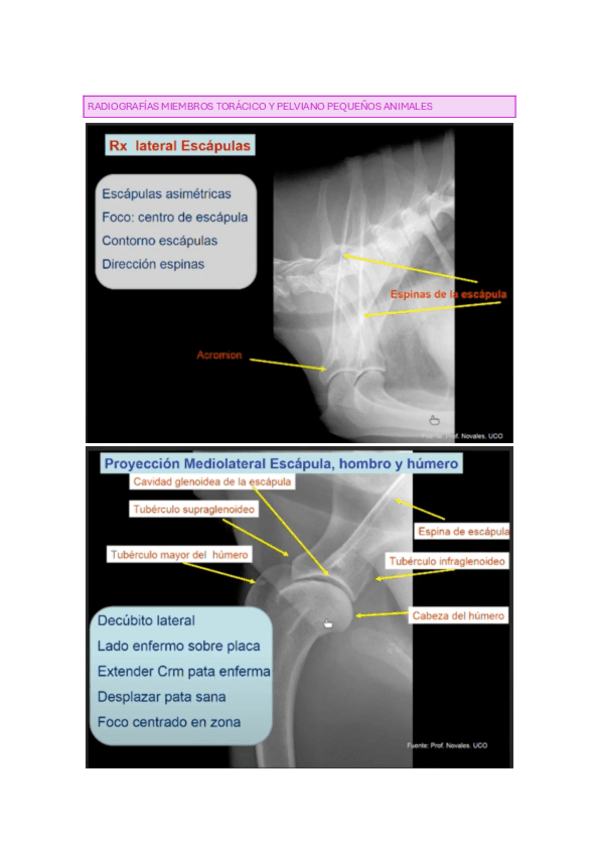

RADIOGRAFIAS-MIEMBROS-TORACICO-Y-PELVIANO-PEQUEN240127191112.pdf

Tema-7b.-Miembro-pelviano.pdf

Tema-7a.-MT-perro.pdf